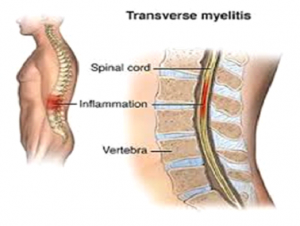

میلیت عرضی یک اختلال است که به دلیل التهاب طناب نخاعی ایجاد شده و هر دوسمت سگمان نخاعی درگیر شده را دربرمی گیرد.

واژه میلیت (myelitis) نشان دهنده التهاب طناب نخاعی و واژه ( transverse) به الگویی که این اختلال باعث تغییر حس می شود باز می گردد.

در واقع واژه عرضی نشان می دهد که در سطح مشخصی از طناب نخاعی این اختلال معمولا ایجاد می شود.